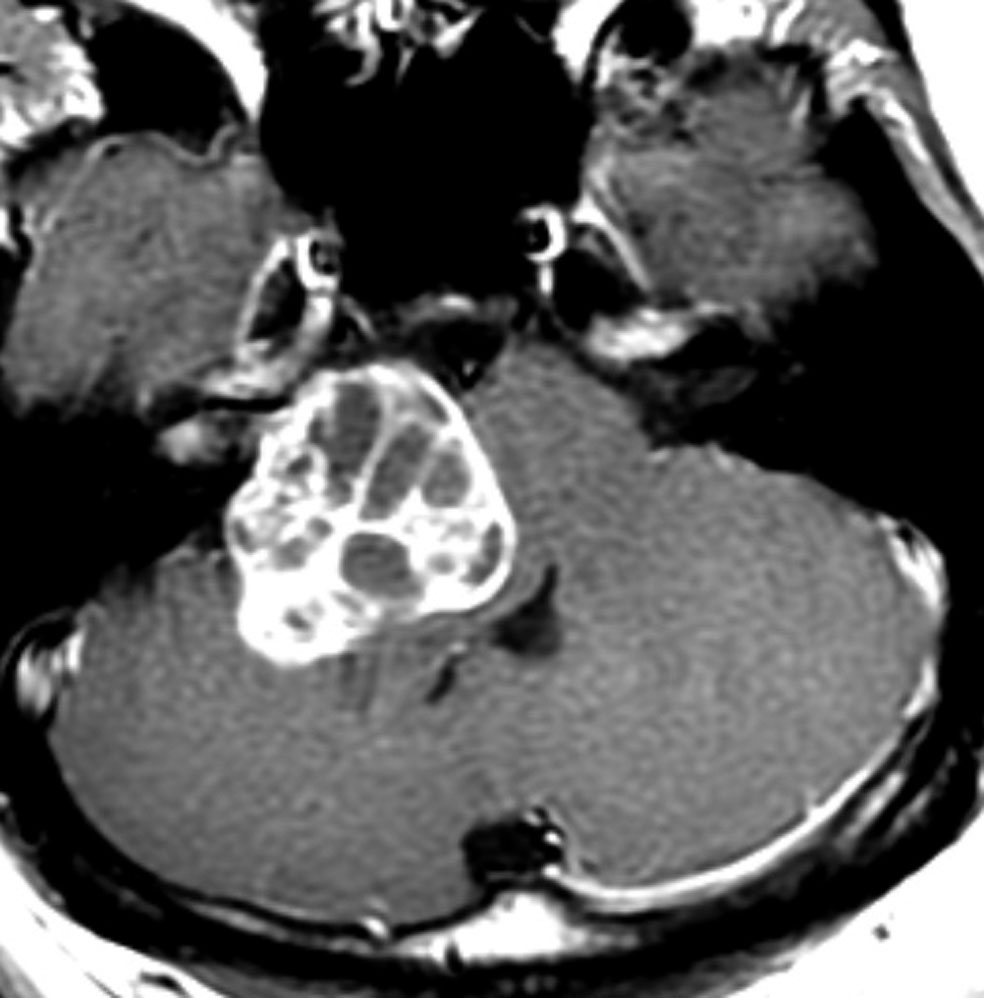

腫瘍が嚢胞性拡大で大きくなって,腫瘍内出血して,閉塞性水頭症になって意識障害を生じた患者さんです。このような事態になると臨時手術で腫瘍を摘出します。

大きなのう胞性聴神経腫瘍です。いくつかの袋が重なって腫瘍を形成しています。橋や延髄(脳幹部)が変形して,第4脳室がつぶれて閉塞しています。袋の周りが白く線状に造影されているのですが,この袋の壁だけに腫瘍細胞がありますから,これを剥がすように摘出します。顔面神経が薄くなって袋の壁にくっついているのですが,袋を破ってくしゃくしゃにすると顔面神経の位置が変わってしまって,顔面神経を損傷することがあるので要注意です。のう胞性聴神経腫瘍の方が顔面神経麻痺の後遺症の頻度が高いという報告もあるくらいです。この患者さんは迷走神経と舌咽神経の圧迫も強くて,ご飯を飲み込むことが難しくなっていました(嚥下障害)。

また,この患者さんは急に容態が悪くなって意識障害となりました。何故なら腫瘍の内部で出血したからです(黄色の矢印の部分)。第4脳室が詰まって閉塞性水頭症になって側脳室が拡大しています(右の画像)。